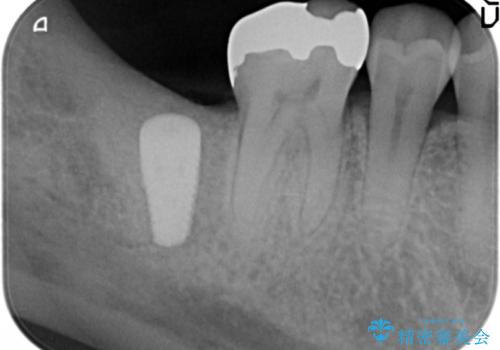

X線写真より根尖付近までの骨吸収を認めます。

抜歯を余儀なくされる状況ですが、将来的にインプラントによる咬合機能回復を希望されたので抜歯と同時に骨補填剤を填入し骨の造成をしたのちのインプラント治療を計画します。

歯を失い、将来的にインプラントを埋入し咬合機能を回復していく場合、十分な骨量の確保は重要です。

今回抜歯後、骨が十分に確保できないとの判断から抜歯と同時に骨補填剤の填入を行いました。